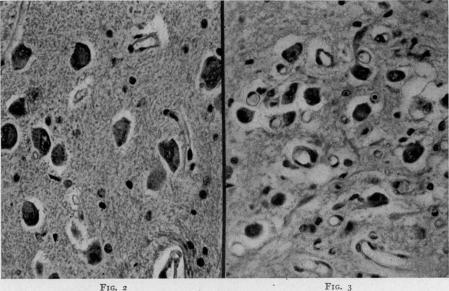

Studies on the Toxemia Syndrome After Burns II: Central Nervous System Changes as a Cause of Death.

Ann Surg. 1945 Mar;121(3):301-13. doi: 10.1097/00000658-194503000-00005.